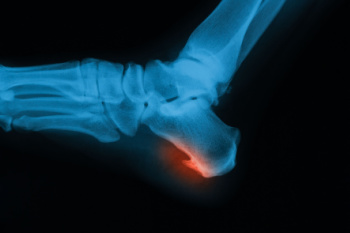

Cuboid syndrome is a foot condition where the cuboid bone, located on the outer side of the foot, becomes partially dislocated or misaligned. This misalignment causes pain and discomfort primarily felt along the lateral side of the foot, often extending to the base of the fourth and fifth toes. The peroneus longus muscle, which runs along the outer calf and attaches to the cuboid bone, plays a role in this condition. When the peroneus longus is overly tight or strained, it can pull on the cuboid bone, contributing to its misalignment. This can occur due to sudden twists or excessive weight-bearing activities. Proper diagnosis and treatment, including rest and sometimes manipulation of the cuboid bone, are essential for alleviating pain and restoring normal foot function. If you have pain in this part of your foot, it is suggested that you schedule an appointment with a podiatrist who can effectively diagnose and treat cuboid syndrome.

Cuboid syndrome is a common cause of lateral foot pain, which is pain on the outside of the foot. The condition may happen suddenly due to an ankle sprain, or it may develop slowly overtime from repetitive tension through the bone and surrounding structures.

A common symptom of cuboid syndrome is pain along the outside of the foot which can be felt in the ankle and toes. This pain may create walking difficulties and may cause those with the condition to walk with a limp.

Diagnosis of cuboid syndrome is often difficult, and it is often misdiagnosed. X-rays, MRIs and CT scans often fail to properly show the cuboid subluxation. Although there isn’t a specific test used to diagnose cuboid syndrome, your podiatrist will usually check if pain is felt while pressing firmly on the cuboid bone of your foot.